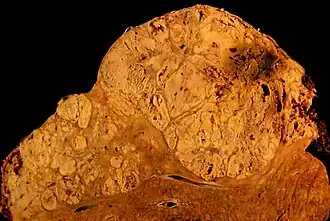

Anatomía patológica

La anormalidad principal de la cirrosis hepática es la presencia de fibrosis, que consiste en el depósito de fibras de colágeno en el hígado. Pero para que se pueda hacer el diagnóstico anatomopatológico de cirrosis, este acúmulo de fibras ha de delimitar nódulos, es decir, ha de aislar áreas de tejido hepático, alterando la arquitectura del órgano y dificultando la relación entre los hepatocitos y los finos vasos sanguíneos a través de los cuales ejercen su función de síntesis y depuración y a través de los cuales se nutren.

De modo esquemático, la fibrosis forma algo parecido a una red tridimensional dentro del hígado, en la que las cuerdas de la red serían la fibrosis y las áreas que quedan entre las mismas los nódulos de células que regeneran dentro del mismo. Esta alteración se denomina nódulo de regeneración y es la característica que permite establecer el diagnóstico de cirrosis. Existen otras alteraciones hepáticas que se acompañan de fibrosis, que no se consideran cirrosis al no cumplir la condición de formar nódulos de regeneración.